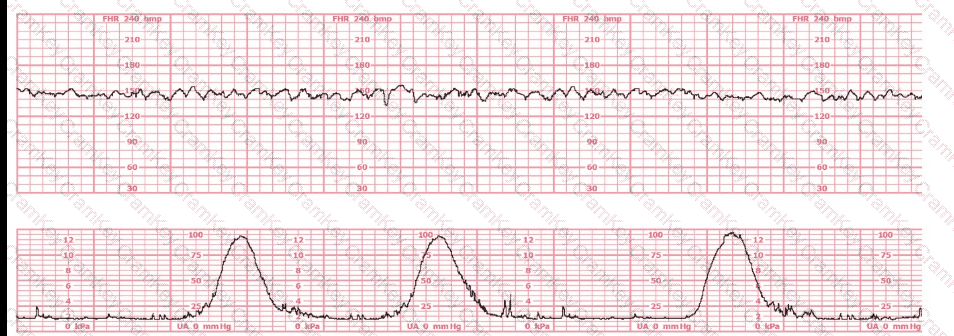

This tracing reflects

Questions 17

Options:

A.

Minimal variability

B.

Moderate variability

C.

Sinusoidal pattern

Discussion